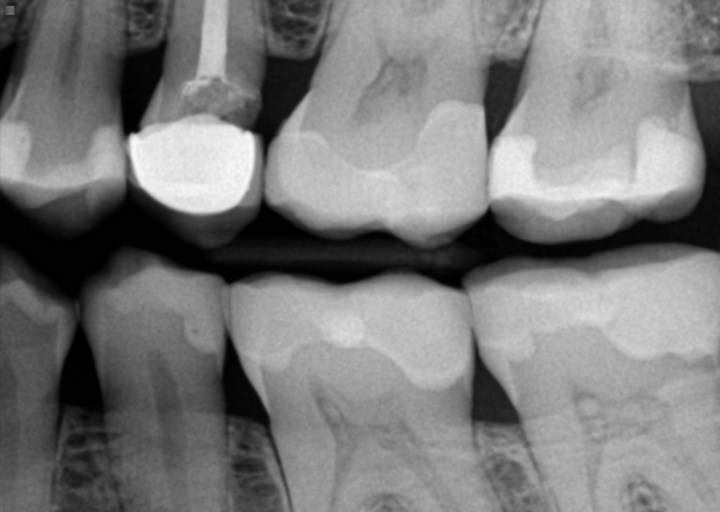

Sometimes it is necessary to adjust the opposing tooth when a new restoration is placed in order to maintain the integrity of the restoration.  However, if several teeth are being adjusted, there may be an additional reason why.  These adjustments to your tooth structure should be very minimal and should not cause any discomfort.  Initially, some cold sensitivity may arise, but should subside quickly.  The crown in the picture provided, appears to be similar to the size and shape of tooth #30.  When a dentist finds it necessary to adjust adjacent teeth, your permission should be given prior to the procedure.  If your teeth are causing discomfort and you have additional questions regarding your treatment, you should speak to your dentist and allow he/she to provide feedback and an explanation for the additional treatment.